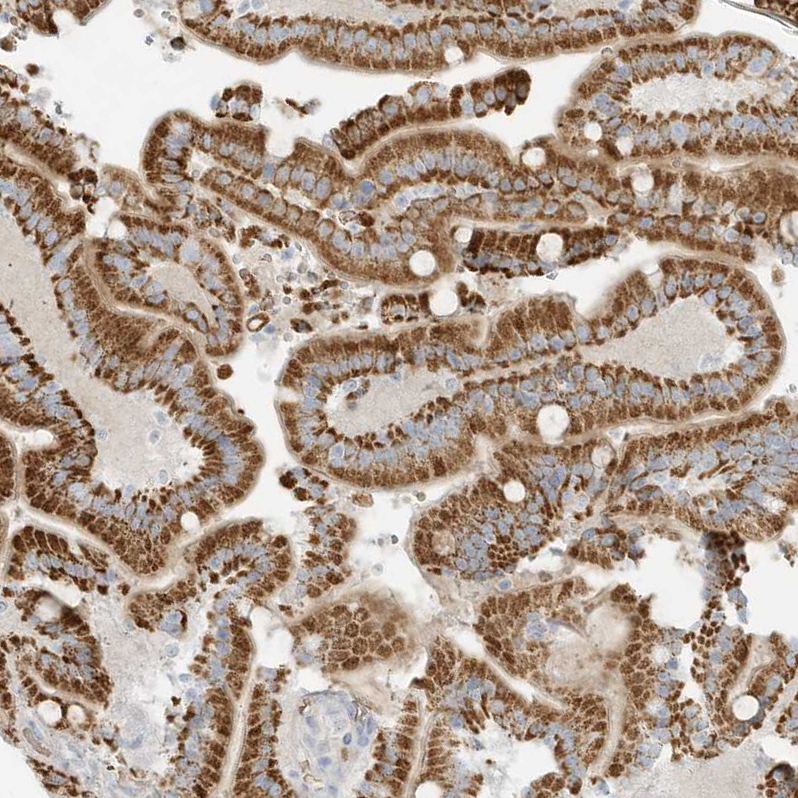

Immunohistochemical staining of human heart muscle shows weak cytoplasmic positivity in cardiomyocytes.